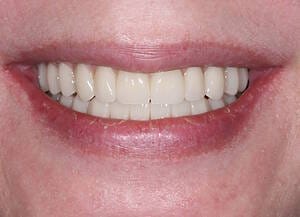

The moment Natalie saw her new smile, the emotion was undeniable. What had once been a source of discomfort, anxiety, and embarrassment had been completely transformed. Her new teeth restored full function and aesthetics, giving her back the ability to eat, speak, and smile without hesitation.

This result was more than cosmetic. It marked the end of a long journey filled with fear and hesitation, and the beginning of a new chapter defined by confidence and well-being. Natalie’s story is a powerful example of how modern dentistry, when led by skilled professionals and supported by cutting-edge technology, can restore much more than teeth.

My first look in the mirror with my new set of teeth was incredible. I’m in disbelief and I feel a bit overwhelmed because it looks so good. At the same time, it looks so natural, it is the shape of my natural teeth and smile. They feel comfortable, I can speak with them. I feel very confident that this will work very well for me.